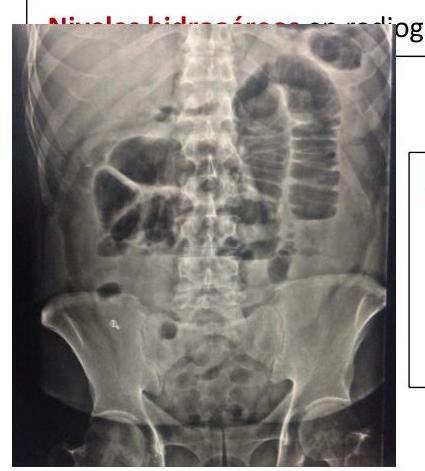

# OCLUSIÓN INTESTINAL ## DEFINICIÓN Se define como la **INTERRUPCIÓN DEL TRÁNSITO INTESTINAL**, lo que impide expulsar gases y heces por el recto. El bloqueo de la luz intestinal se da en su mayoría por factores extrínsecos (adherencias, hernia inguinal, hernia de pared estrangulada) y en pocas ocasiones por obstrucción de la luz. **ADHERENCIAS PERITONEALES**: son bandas fibrosas entre órganos o tejidos o ambos en la cavidad abdominal que normalmente están separados. TIPOS DE ÍLEO | PARALÍTICO / ADINÁMICO | Existe una causa funcional que altera el peristaltismo. La causa más frecuente es la cirugía abdominal (íleo reflejo postquirúrgico). Tras la cirugía, el intestino delgado es el primero en recuperar la movilidad a las 24 horas, seguido del estómago 48 horas, el colon tarda 3 -5 días. | | :--: | :-- | | OBSTRUCTIVO / MECÁNICO | Existe una causa orgánica que lo produce como son las barreras físicas que obstruyen la luz. | | ESPÁSTICO | Hiperactividad descoordinada del intestino que se observa en la intoxicación por metales pesados, porfiria y uremia. Se debe tratar la enfermedad sistémica. | | ÍLEO DE LA OCLUSIÓN VASCULAR | Movilidad descoordinada del intestino isquémico | ## EPIDEMIOLOGÍA - LAS **ADHERENCIAS SON LA CAUSA MÁS COMÚN DE OCLUSIÓN INTESTINAL** - Responsables en 65 - 75 % de los casos (mortalidad de 3.5 - 6%) - El 70% de las adherencias responde a manejo conservador, un 30% requiere manejo quirúrgico. - En el intestino delgado, la obstrucción mecánica es el trastorno quirúrgico más frecuente. ## FACTORES DE RIESGO - Adherencias - **Hernia inguinal** (primera causa en pacientes sin cirugía previa) - **Hernia de pared estrangulada** - Neoplasias - Íleo por cálculo biliar - **Enfermedad de Crohn** - **Vólvulo** - **Intususcepción** - Divertículo de Meckel - **Cuerpo Extraño** # CLÍNICA - **DOLOR ABDOMINAL TIPO CÓLICO** + **NÁUSEA**, **VÓMITO** Y **ESTREÑIMIENTO** - El vómito es más prominente en las obstrucciones proximales - La distensión se asocia al íleon distal. - Los ruidos intestinales son hiperactivos al principio, luego son mínimos | INTESTINO DELGADO | Dolor abdominal, vómitos (fecaloides si es distal), distensión abdominal, hiperperistaltismo con ruidos metálicos | | :--: | :--: | | INTESTINO GRUESO | Dolor y distensión abdominal Vómitos y estreñimiento Incapacidad de expulsar gases y heces | **Obstrucción Estrangulada**: Dolor abdominal desproporcionado, taquicardia, fiebre, leucocitosis y acidosis. ## DIAGNÓSTICO **GOLD STANDARD: RADIOGRAFÍA DE ABDOMEN** (En decúbito y de pie) + Tele de Tórax de pie. ## TRIADA DE RX: - Asas en Intestino delgado dilatadas (+3 cm de diámetro) - Niveles hidroaéreos - Escasez de aire en el colon  Radiografía en decúbito con dilatación de asas de intestino delgado con válvulas conniventes (separado de la base y por el extremo en contacto)  Signo de Collar de Perlas: representa pequeñas cantidades de aire atrapado en las válvulas del intestino delgado, predominantemente lleno de líquido. Se presenta en obstrucción mecánica de ID. DATOS EN **TAC**: 1. Dilatación proximal del intestino 2. Descompresión distal del intestino 3. Contraste luminal que no pasa más allá de la zona de transición 4. Colon con poco gas o líquido 5. Signo de las heces (burbujas)   Signo de **PILAS DE MONEDAS**: Pliegues intestinales engrosados, lisos, rectos y perpendiculares al eje longitudinal de la luz. # TRATAMIENTO ## CONSERVADOR ## SONDA NASOGÁSTRICA / TUBO INTESTINAL LARGO - El 90% de las obstrucciones de ID se resuelven con **SNG y REPOSICIÓN HIDROELECTROLÍTICA** - Debe mantenerse durante 48 - 72 horas. - Si existe obstrucción por estrangulación, obstrucción maligna, hernias encarceladas, cuerpo extraño, enteritis por radiación, peritonitis o abdomen agudo, debe considerarse **cirugía**. ## QUIRÚRGICO Deberá considerarse el manejo invasivo en los siguientes casos: A. **Íleo mecánico intestinal por más de 3 días** B. Drenaje por SNG al tercer día >500 ml C. Edad menor a 40 años o adherencias complejas D. **Obstrucción completa** del intestino delgado (sin aire en intestino grueso) y CPK mayor a 130 Considerar **Cirugía INMEDIATA** en los siguientes casos: - Cirugía dentro de las 6 semanas previas al cuadro de oclusión - Cuadro no resuelto con manejo conservador en las 48-72 horas a pesar de utilizar medio de contraste hidrosoluble por SNG - Presencia de líquido intraperitoneal, edema del mesenterio y signo de las heces en intestino delgado - Dolor abdominal mayor a 4, resistencia abdominal, leucocitos 10,000 o más, PCR 75 mg - Datos de **estrangulación**: fiebre, taquicardia, leucocitosis, acidosis metabólica. ## LAPAROTOMÍA EXPLORADORA 1. La incisión debe permitir tener una adecuada exposición y visibilidad 2. Identificar sitio y causa de obstrucción, si no es obvio, hay que descomprimir el intestino hasta encontrarla 3. Si el intestino está isquémico hay riesgo de ruptura con salida de contenido a cavidad abdominal 4. Después de corregir obstrucción se deben explorar los cuatro cuadrantes. 5. Si es requerido, realizar resección intestinal y anastomosis primaria. ## LAPAROSCOPÍA Solo se realizará en un grupo selecto de pacientes como abordaje - Casos de un primer episodio de oclusión intestinal por **adherencias** - Diámetro intestinal menor a 4 cm . - Sospecha de una banda - Antecedente de 2 o menos laparotomías - Antecedente de apendicectomía o colecistectomía puede someterse a laparoscopía. # ANEXOS